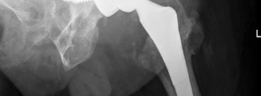

For anyone wondering about Acetabular Revision: Solving Challenges Post Two-Stage Arthroplasty, A **title acetabular revision** is a complex procedure addressing issues like septic loosening, dislocation, and significant osteolysis in total hip arthroplasty. For a 71-year-old male with a dislocated left THA due to infection and periacetabular bone loss, treatment involved a two-stage exchange followed by revision with a press-fit hemispherical cup and screw fixation.

These defects can typically be managed with a hemispherical, highly porous metal (tantalum or titanium foam) multi-hole acetabular component. The porous metal provides a high coefficient of friction for initial scratch fit and an optimal scaffold for biologic ingrowth. Particulate allograft may be used to fill contained cavitary defects prior to cup insertion. Multiple screws are placed into the safe zones of the ilium and ischium to maximize initial stability.

These defects are characterized by superior and lateral bone loss but retain greater than 50% host bone contact. Reconstruction often involves a "jumbo cup" (typically greater than 62mm in males and 58mm in females) combined with highly porous metal augments.

The augment is trialed and fixed to the superior ilium using screws, effectively converting the uncontained defect into a contained one. The hemispherical cup is then impacted and cemented into the augment, or a modular system is utilized where the cup and augment are mechanically linked.